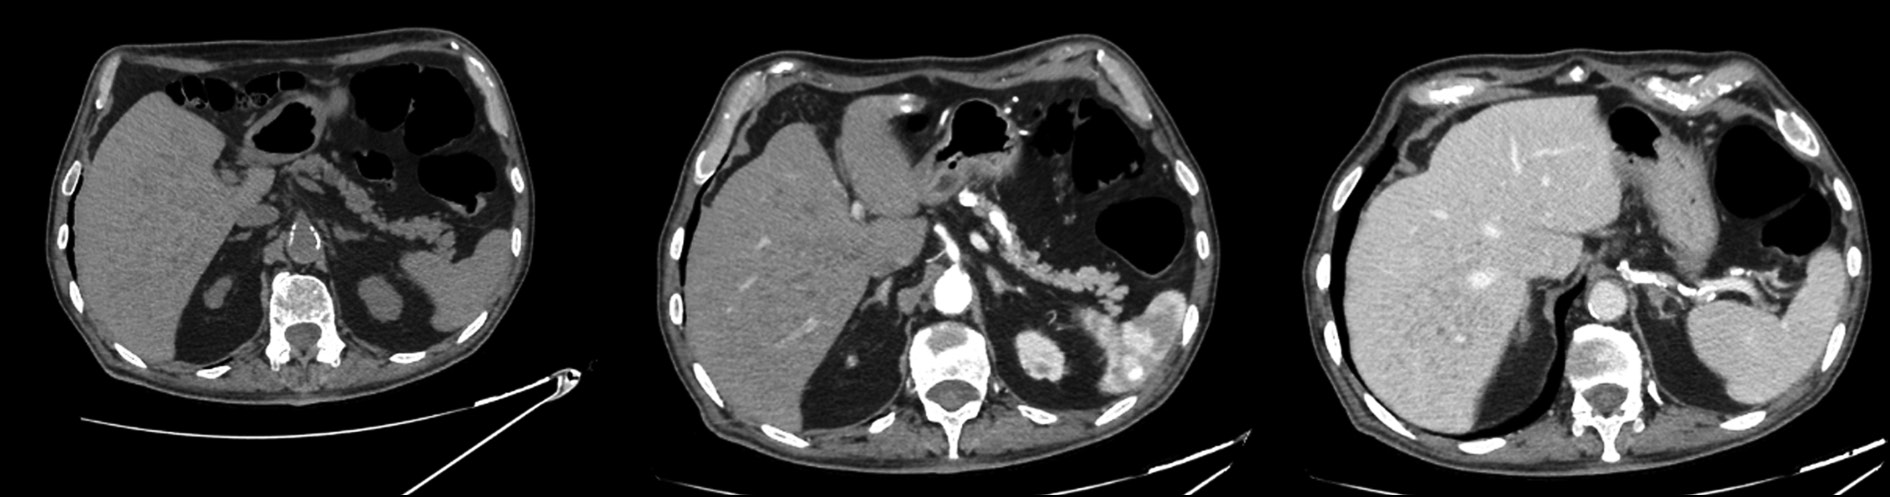

Multiple biliary hamartomas are a benign incidental finding in the liver. They are not easily detected if one has never seen them, and if appropriate imaging tests are unavailable, and also can be challenging to differentiate from other liver lesions based on imaging alone. Thus, this study aimed to expand the radiologist’s digital image library, enabling a quick and precise differential diagnosis. This paper also highlights the importance of thorough radiological assessment and need for a multidisciplinary approach, involving radiologists, hepatologists, and pathologists, to ensure a precise diagnosis.

The patient presented at the hospital for a computed tomography scan and an abdominal magnetic resonance imaging recommended by his general practitioner to assess the biliary tree (magnetic resonance cholangiopancreatography), owing to persistent abdominal pain. The patient had never undergone an abdominal magnetic resonance imaging previously; hence, the discovery of hepatic lesions was incidental and unexpected.

Magnetic resonance imaging revealed multiple benign lesions in both the hepatic lobes comparable to the Von Meyenburg complex. These lesions are multiple hamartomas and behave differently in all magnetic resonance imaging sequences.

Images acquired with different magnetic resonance imaging sequences were carefully examined. Multiple lesions were found scattered throughout the liver; however, the lesions were benign and consistent with the diagnosis of multiple biliary hamartomas.